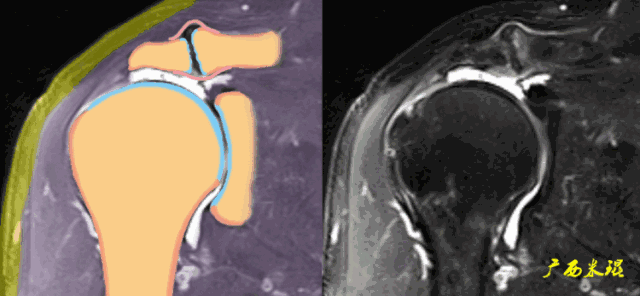

2、斜矢状位:垂直于冈上肌长轴,观察肩峰形态及喙肩弓,观察肩袖4个组分的短轴断面。

3、轴位:平行于关节盂/垂直于盂肱关节,主要评估盂唇,同时兼顾肩胛下肌、冈下肌及小圆肌。

1、信号异常

肩袖出现3级信号,是诊断的直接征象,一旦发现3级信号,肩袖撕裂无疑。

a、肩袖关节侧出现3级信号,部分撕裂。

b、肩袖滑囊侧出现3级信号,属于部分撕裂。

c、肩袖内部出现大范围3级信号,属于部分撕裂。

d、肩袖出现3级信号,关节侧撕裂回缩,也属于部分撕裂。

e、肩袖出现3级信号,肩袖完全中断,属于完全撕裂但无回缩。

2、形态异常

肩袖可以变薄、变厚或不规则,但只有中断才是3级信号,肩袖中断后断端回缩,肌肉萎缩也是肩袖撕裂的直接征象。